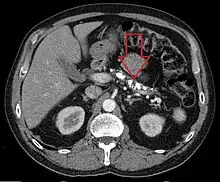

| Axial CT showing multiple calcifications in the pancreas in a patient with chronic pancreatitis | |

Computed tomography, magnetic resonance cholangiopancreatography (MRCP), and endoscopic ultrasound (EUS) all have similar sensitivity and specificity for diagnosing chronic pancreatitis.[4] MRCP is particularly utilized for its sensitivity in imaging the pancreatic ducts and bile ducts for associated changes such as stones or strictures.[4][12] A biopsy of the pancreas is not required for the diagnosis.[4] On imaging, pancreatic and bile duct dilatation, atrophy of the pancreas, multiple calcifications of the pancreas, and enlargement of pancreatic glands can be found.[12]